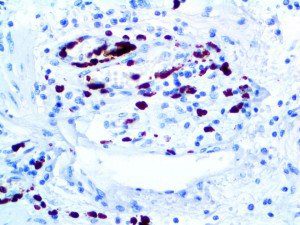

It is the ICU physician who is most likely to witness one of the deadliest manifestations of the abnormal immunological response, the cytokine storm syndrome (CSS). This response is also referred to by some as the cytokine release syndrome (CRS). CSS is characterized by continuous activation and expansion of macrophage and lymphocyte populations, which secrete large amounts of cytokines, causing the cytokine storm. This massive cytokine release is akin to hemophagocytic lymphohistiocytosis (HLH) disease, a syndrome characterized by initial unchecked and persistent activation of cytotoxic T lymphocytes and NK cells.

Clinical and laboratory manifestations of HLH include fever, enlarged liver and/or spleen, neurologic dysfunction, coagulopathy, liver dysfunction, cytopenias (i.e., low levels of erythrocytes, leukocytes, and/or platelets), hypertriglyceridemia, hyperferritinemia, hemophagocytosis, and eventually diminished NK cell activity as the immune system becomes progressively paralyzed. HLH can be familial (primary HLH) or secondary to another disease process (sHLH), such as rheumatic disease, in which it is referred to as macrophage activation syndrome (MAS, characterized by elevated ferritin).

This activation induces inflammatory monocytes to highly express IL-6, starting a localized and then systemic cascade effect that results in hyperproduction of IL-6, which accelerates the inflammatory process. Because IL-6 also increases vascular permeability, excessive levels cause blood vessels to become very leaky. This, along with clotting factors released from vascular endothelial cells, stimulates the coagulation cascade, resulting in microthrombosis (tiny clots), which leads to ischemia and tissue death of the kidney, intestines, heart, liver, brain and extremities.